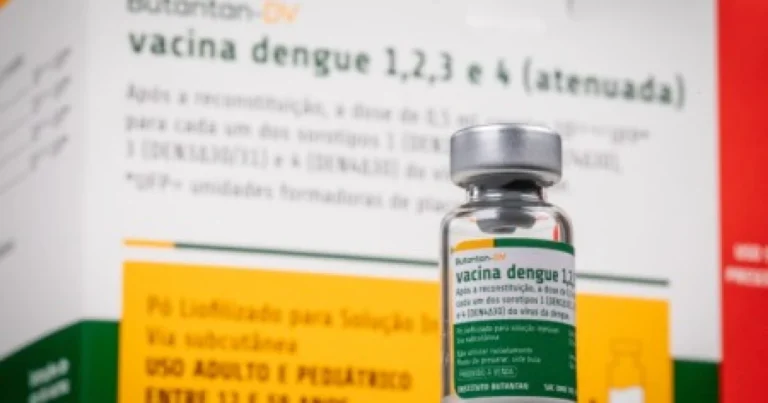

Vacina brasileira contra dengue tem 80,5% de proteção contra casos graves, diz pesquisa

A vacina tetravalente contra a dengue desenvolvida pelo Instituto Butantan, com apoio da Fundação de Amparo à Pesquisa do Estado…